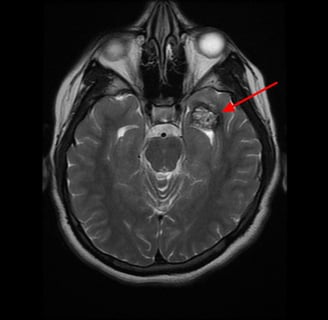

O diagnóstico de cavernoma é frequentemente feito por meio de ressonância magnética (RM) cerebral, que oferece alta sensibilidade para detectar essas lesões. As principais características radiológicas incluem:

Aspecto “popcorn”: Presença de áreas heterogêneas que representam hemorragias recentes e antigas, tecido fibroso e calcificação.

Halo Hipointenso em T2: Este sinal é causado pela deposição de hemossiderina ao redor da lesão, indicando hemorragias prévias.

Realce Mínimo ou Inexistente: Diferencia os cavernomas de outras malformações vasculares, como angiomas venosos ou arteriovenosos.